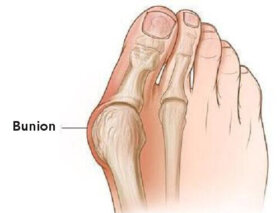

건막류는 발에 생기는 가장 고통스럽고 가장 흔한 변형 중 하나이다. 대부분 발에 맞지 않는 신발을 신은 결과로 발생하지만, 유전적인 문제인 경우도 있다. 오늘 이 글에서는 자연적으로 건막류를 예방하는 방법을 공유한다. 발의 건막류 상태를 가장 빨리 개선하는 방법의 하나는, 소염제와 진통제를 사용해서…